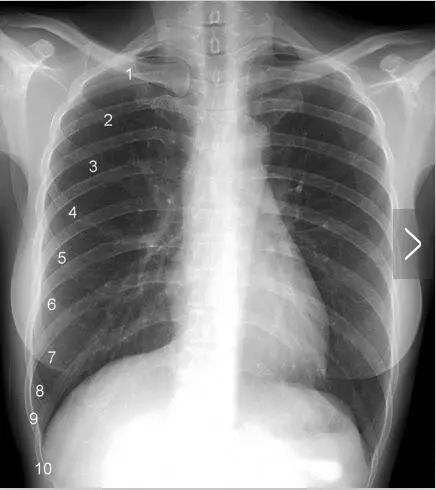

右横隔膜は第 10 後肋骨もしくは第 6 前肋骨の高さにある。肺が過膨張を示すと、横隔膜は 低下 する。(側面像では、胸骨と上行大動脈の間が増加する) ・左横隔膜の下には 胃泡 と 横行結腸脾湾曲 の空気が見える。Costae 関連情報 MeSH Ribs グレイの解剖学 書籍中の説明(英語) テンプレートを表示 人間 の肋骨は全部で二十四本で両側に十二本ずつ、それぞれ第一肋骨~第十二肋骨と名前が付いている。 そのうち第一肋骨~第七肋骨は 胸骨 外側縁と接しており完全に胸部を覆っているのに対して、第八肋骨~第十二肋骨は胸骨と接しておらず前腹部は開いている。体幹回旋動作は、主に股関節を中心とした下肢の報告が多く胸郭との関連を述べたものは少なかった。 今までの報告によると体幹回旋動作と胸郭の関係は十分に明らかにされていなかった。 本研究では胸郭拡張差 (腋窩レベル、剣状突起レベル、第10肋骨

前胸部的肺下界始于第6 肋骨,向两侧斜行向下,于锁骨中线处达第6 肋间隙,至腋中线处达第8 肋间隙。后胸壁的肺下界几乎呈一水平线,于肩胛线处位于第10 肋间隙水平。 6、胸 膜:可分为脏胸膜和壁胸膜。其中脏胸膜覆盖在肺的表面,壁胸膜则覆盖在胸廓内表面、膈上面及纵隔面。 肺叶之间由正中の第二肋間は気管分岐部であり,正に胸部の診察の要である。 第四肋間は通常,乳首の高さであり,v4誘導(第五肋間と左鎖骨中線の交点)は左乳首のすぐ下になる。 ずれているときは確認。 V1(赤) 第4肋間胸骨右縁 V2(黄) 第4肋間胸骨左縁 ③下葉はわき(腋窩)とTh2を結んだ線と第10肋骨との間にあります Th2 も 第10肋骨もさきほど見つけてあるので簡単です こうして見てもらうとわかると思いますが、後ろから見た時ほとんどが下葉なんですね、大っきいでしょ 参考までに別の第10肋骨の

肋骨的生理結構特點決定了最易折斷的部位,第 1—3 肋骨較短,且有鎖骨、肩胛骨保護,較少發生骨折。第 4—7 肋骨較長且位置固定,最容易發生肋骨骨折。第 8—10 肋骨雖長,但與與胸骨形成肋弓,彈性較大不易折斷。第 11—12 肋骨處於前端游離,也不易骨折。第8肋間となる 第4~第5胸椎の高さで、 左右の気管支に分かれる 左下葉:第4~第10 肋骨 XPは背面の肋骨 の方が鮮明に写 っています。 情報誌担当 TomomiM <前面> 右上葉:第4肋骨より 上の前胸部 右中葉:第4から6肋 骨に挟まれた部位 近までの前胸部測定部位는 肩(第4肋骨), 背(最後肋骨), 腰(最後要樞), 3部分의 正中 线에서 좌측 或 右側 5Cm 部分을 測定하여 그 平均値를 利用하고 測定器機가 Bmode인 境遇 測定部位는 背(第10肋骨)의 正中线에서 左側 或 右側 5cm 部分을 測定한다